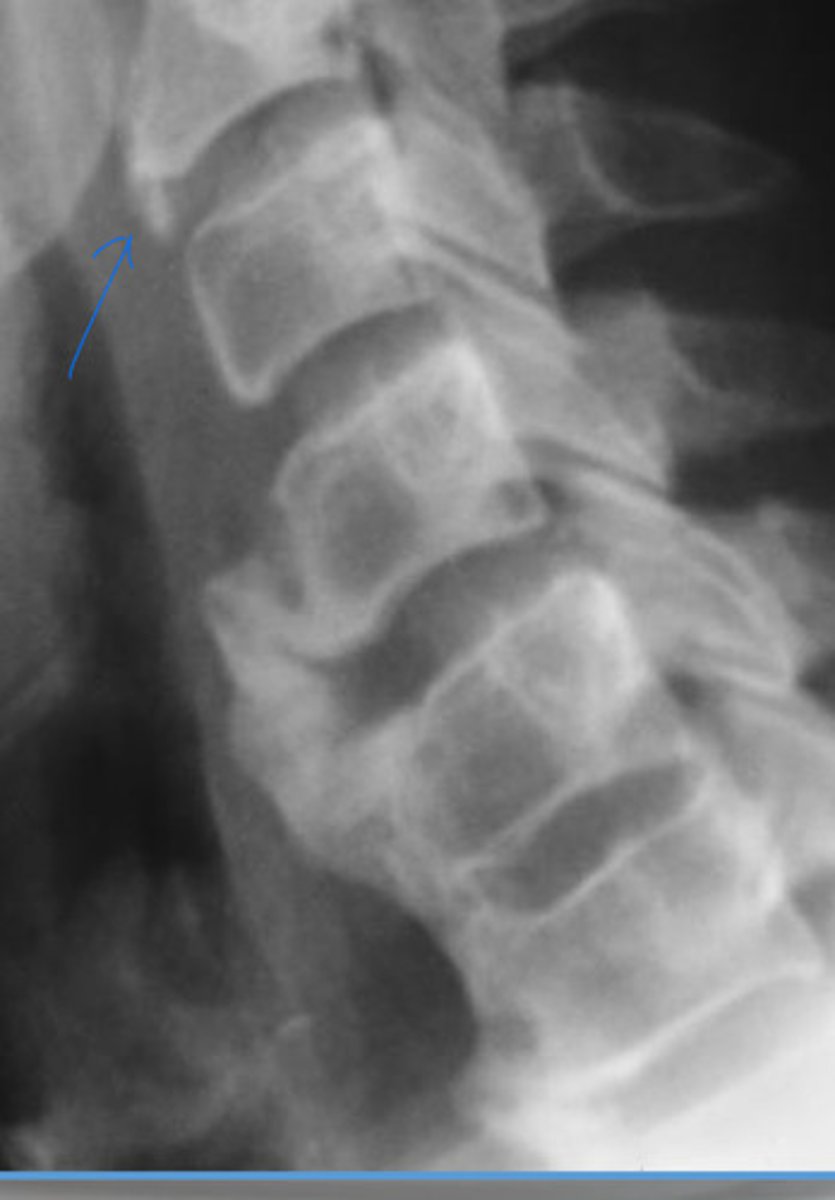

What is the blue arrow pointing at?

DISH (mid body to mid body)

What is the arrow pointing at?

Mid body

Where does the ALL attach to the vertebrae?

DISH (mid body flow of the anterior vertebral line)

What is wrong with this image?